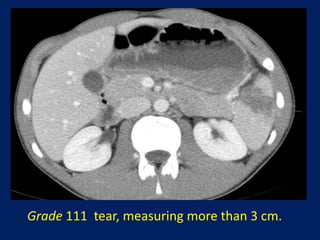

This document discusses imaging of the spleen and summarizes various congenital anomalies and pathologies that can affect the spleen. Some common congenital anomalies mentioned include accessory spleens, asplenia, polysplenia, and splenic fusions. Acquired conditions like repeated infarctions, infiltration, tumors, and cysts can also cause splenomegaly or functional asplenia. Wandering spleen is discussed as a rare congenital anomaly where the spleen lacks attachments and is mobile within the abdomen. Various grades of splenic lacerations and examples of splenic imaging findings are also briefly summarized.